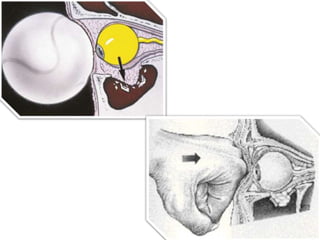

Herniation of orbital fat into the maxillary sinus

61

Image shows depressed fragment of the left orbital floor (arrow)

and an air-fluid level in the left maxillary sinus